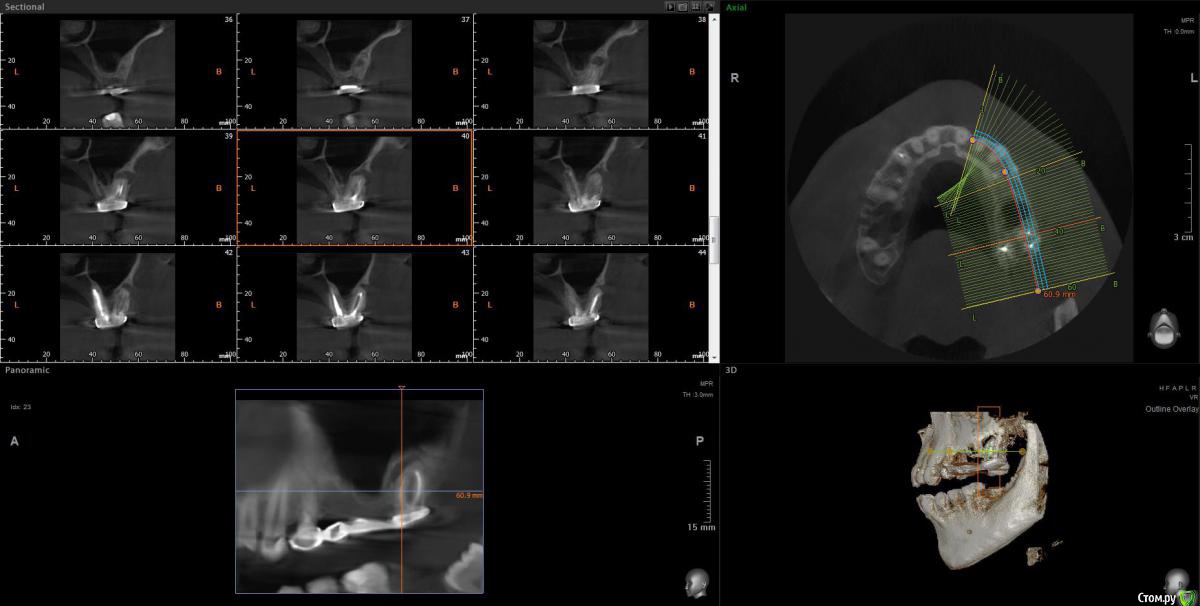

Ботинок Опубликовано 25 июля, 2020 Поделиться Опубликовано 25 июля, 2020 (изменено) Здравствуйте, Спасибо за ваше время для просмотра моей КТ. Речь про 27ой зуб https://drive.google.com/file/d/1yeLfeXNm_Ex4w3dMc1R1VGEqdMZLexYT/view?usp=sharing Жду ответов Изменено 25 июля, 2020 пользователем Ботинок Ссылка на комментарий